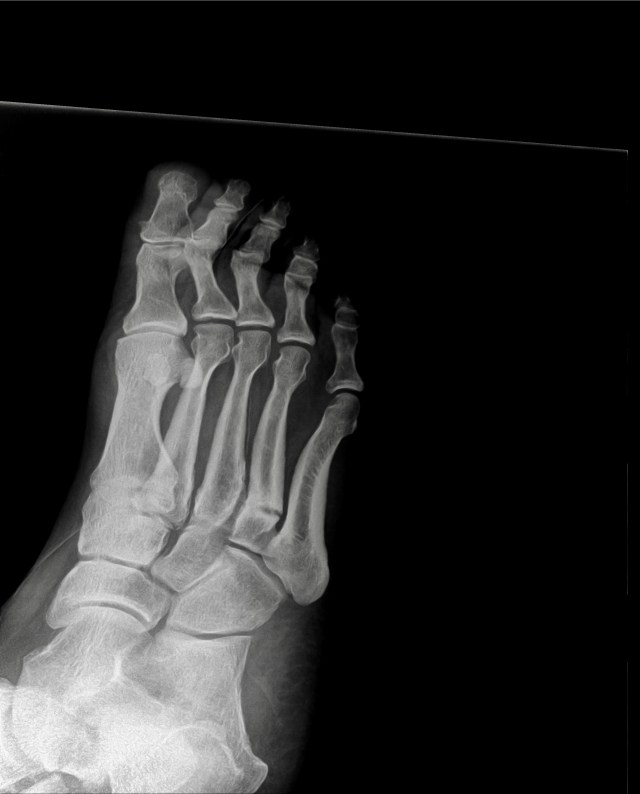

PS: Eight months on and I’m still wearing a boot due to the fractured 4th metatarsal bone. I haven’t been out much with my camera. Poor weather ( typical for Seattle) is also a factor. So, I’ve dug into the archives and re-edited some old film images to post. Just for those doubters, here is the latest X-ray of right foot taken two weeks ago. Little or no healing, so I am now using a device called a Bone Stimulator that attaches to the foot, directly over the fracture. The theory is: wave pulses are sent to the affected area, which is supposed to increase blood flow which = bone growth. Hoping it works!